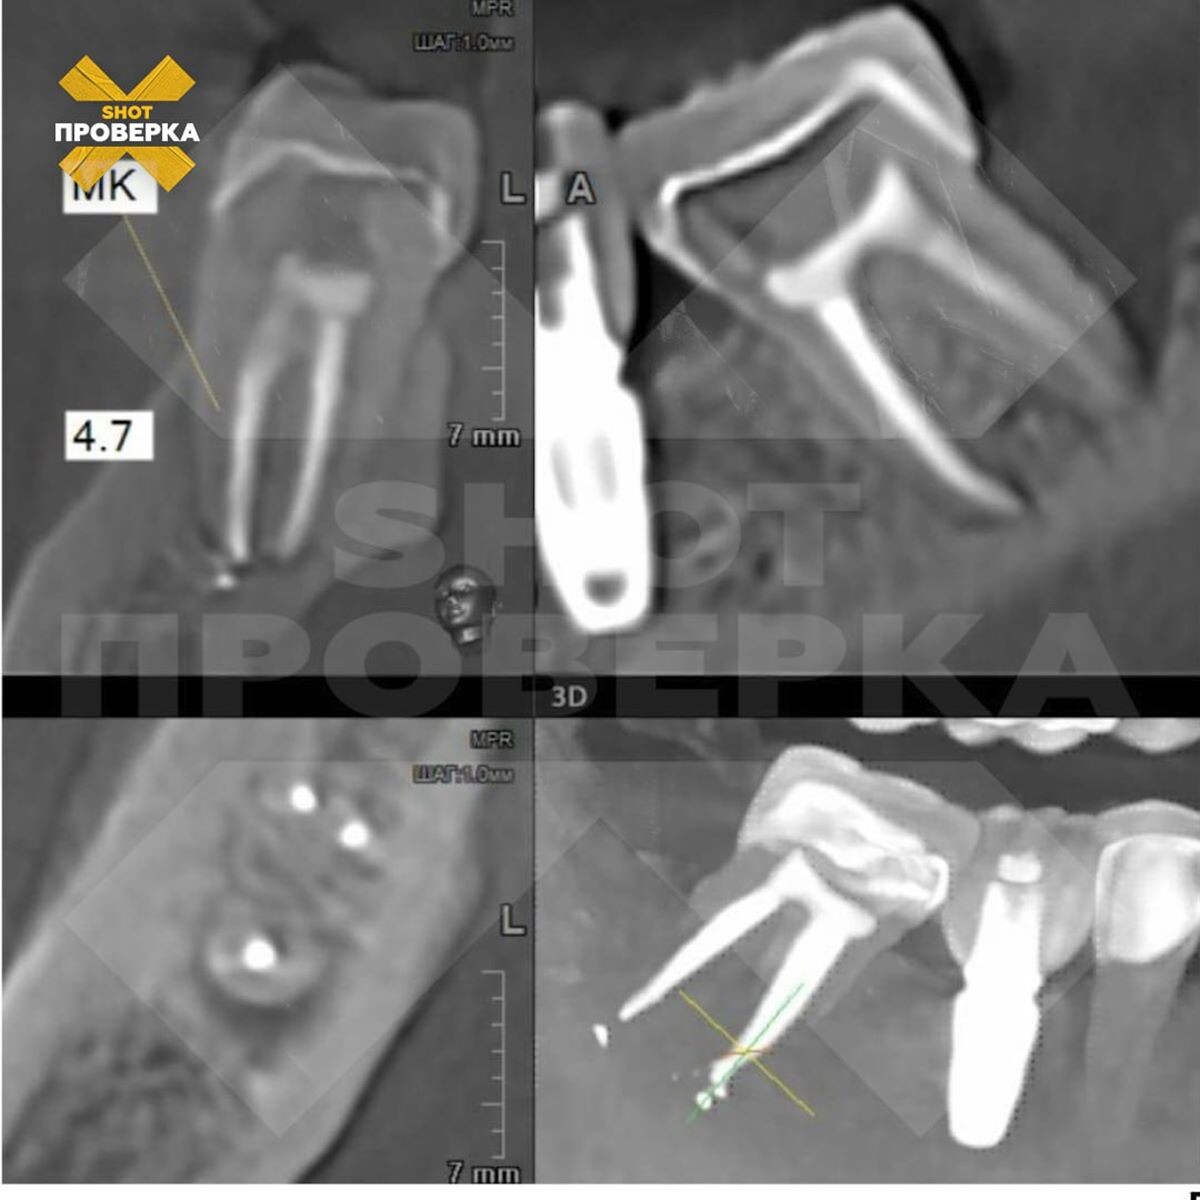

В Краснодарском крае семейная пара хотела «голливудскую улыбку», но получила гнойное воспаление и смещение челюсти за два миллиона рублей; их стоматолог признал факт некачественной работы, но ситуация не улучшилась; судебное разбирательство идёт уже год. Об этом 3 ноября сообщает SHOT ПРОВЕРКА. Инцидент произошёл в Новороссийске. Горожанин вместе с супругой решили привести в порядок передние зубы и обратились в одну из известных клиник города. Принявший их стоматолог убедил пациентов поставить виниры, хотя те не планировали это делать. Цена «голливудской улыбки» составила почти два миллиона рублей. Вместо красивой улыбки пара получила множество проблем. На начальном этапе процедуры, когда удалили нервы, состояние пациентов стало ухудшаться: у мужчины началась сильная головная боль, появилось воспаление, кровоточивость, образовались гнойные нарывы. Несмотря на это, стоматолог пошёл до конца и установил виниры. После установки конструкции выяснилось, что родные зубы горожанина «поехали».

Вместо красивой улыбки пара получила множество проблем. На начальном этапе процедуры, когда удалили нервы, состояние пациентов стало ухудшаться: у мужчины началась сильная головная боль, появилось воспаление, кровоточивость, образовались гнойные нарывы. Несмотря на это, стоматолог пошёл до конца и установил виниры. После установки конструкции выяснилось, что родные зубы горожанина «поехали».

Стоматолог признал, что работа была выполнена некачественно, пообещав всё исправить, но ситуация лучше не стала.